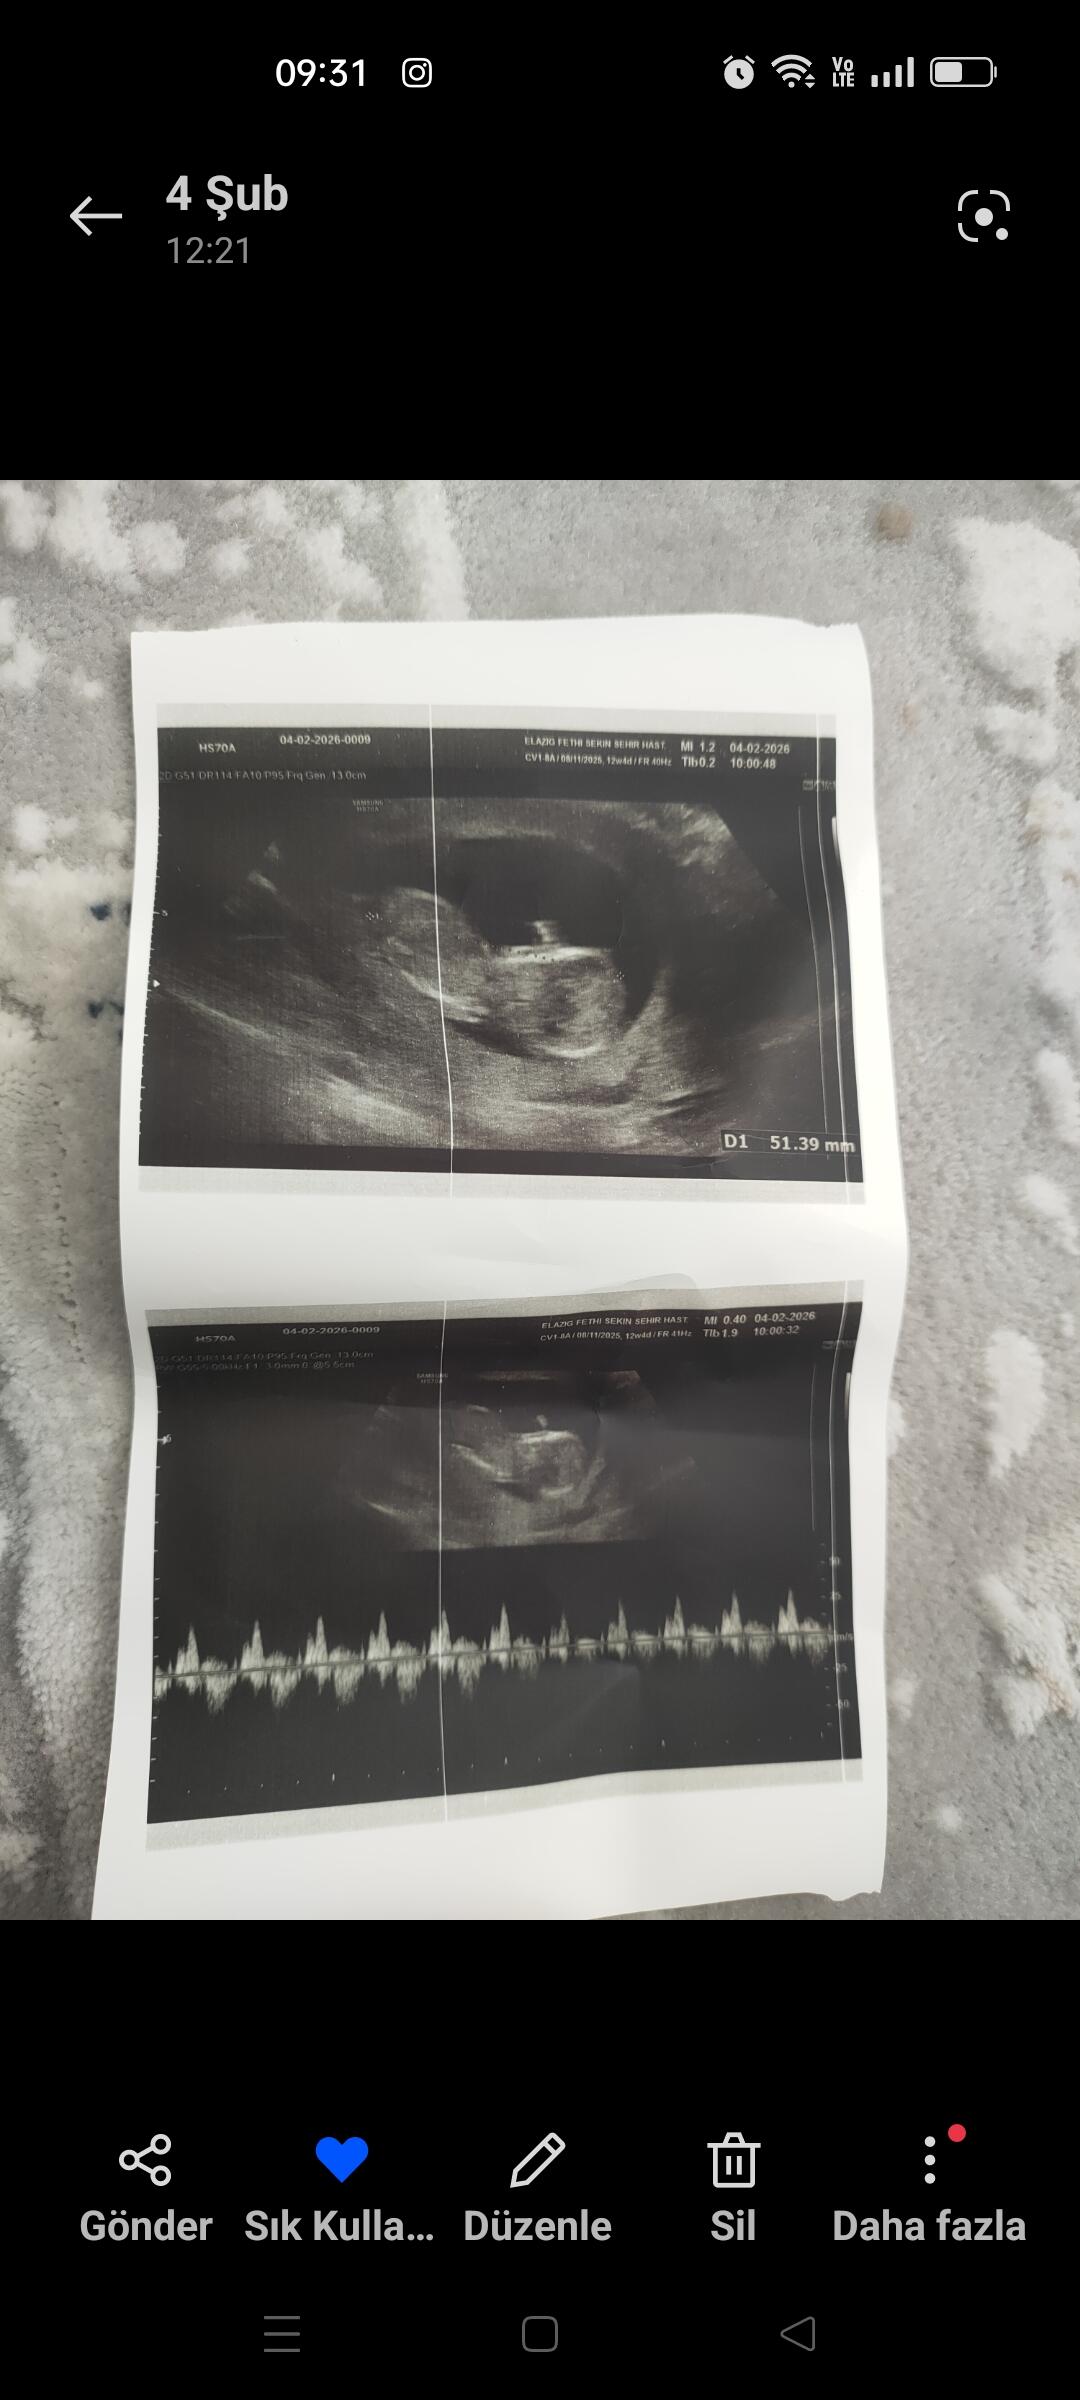

Bende atsam bakarmısınız rica etsem

Atabilirsiniz

Siz ne diyorsunuz tahmininiz

Bacak arasından bir şey var Kordon ise ama kız bebek gibi duruyor canim

Erkek bebek canım ama biraz daha gelişine tekrar at